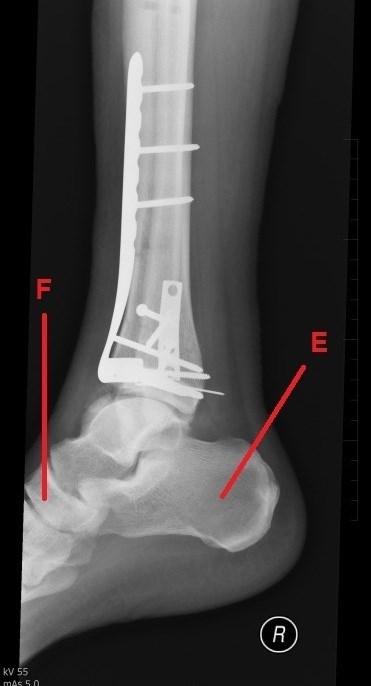

A dál co potřebujete k získání finálních souřadnic? Trocha z té zdravotnické praxe. Správný geokačer má silně vyvinutý smysl pro všímání si detailů, skrytých souvislostí a tak podobně. Princip je jednoduchý. Nepůjde o žádnou kdoví jak složitou matematickou šifru s IT podtextem. V budoucích několika minutách, hodinách či dnech se z Vás stanou radiologové (lékaři zabývající se zobrazovacími technikami) a anatomové. Tak Vás jistě nepřekvapí několik obrázků, na kterých bude vyznačen útvar, který musíte poznat a latinsky (pokud jiným jazykem, tak Vás na to upozorním) pojmenovat. Myslím, že vše bude jasné. Tak jdeme na to…

E -počet písmen v názvu útvaru (latinsky, 1 slovo)

F - počet písmen v názvu útvaru (latinsky, 2 slova)